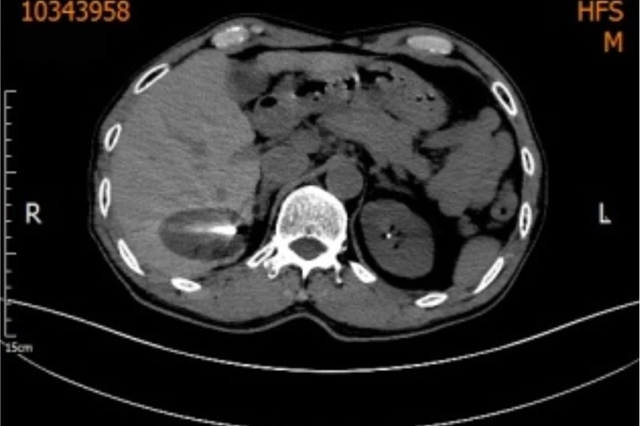

经科室研究讨论后,王晓栋副教授于12月5日为吴先生实施了在CT引导局部麻醉下“肝肿物冷冻(氩氦刀)消融术”。

CT定位引导下,将一根一次性的冷冻消融针,经皮穿刺进入预定靶位后,启动氩氦刀冷冻消融系统。

通入氩气时,产生制冷作用迅速将病变组织整体冷冻至-160℃以下,维持超低温冷冻10分钟,再通入氦气快速升温到零上20℃以上维持2分钟,重复上述冷热循环。

经过两三次的重复,200℃左右温差的极速转换,肿瘤细胞彻底“团灭”最终实现靶区组织坏死,达到了理想的降低肿瘤负荷效果。

手术持续1个半小时过程,中吴先生无任何不适手术很顺利。

术后三天吴大叔就康复出院,定期于肝胆病科门诊复诊,病情一直很稳定。